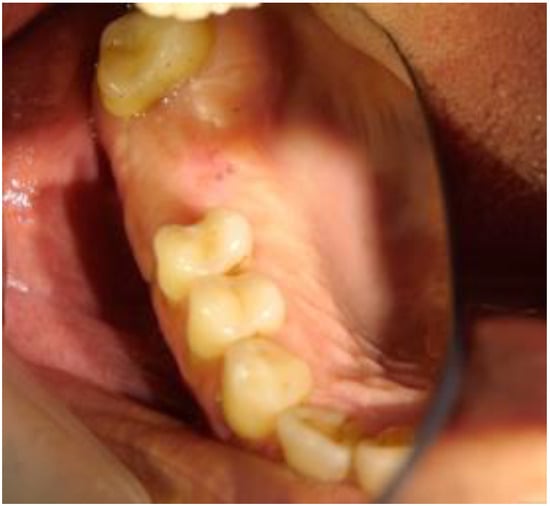

2.1. Clinical and Surgical Procedures